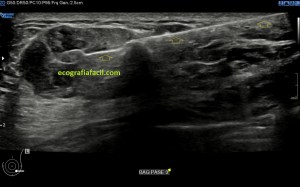

En la imagen 3 ves una imagen de un lipoma, mide 7 cms, la huella de la sonda mide 5cms, la «panoramic view» posee una regla centimetrada que sigue el contorno de la imagen, justo en la profundidad de la misma y lo marca la flecha amarilla. La profundidad la marca la flecha roja y la flecha blanca marca el rango centimetral de los 5cms, fíjate que la línea blanca es ligeramente mayor cada 5 cms. Sirve de referencia, como en la imagen 4 donde ves una colección en el glúteo de más de 10 cms.